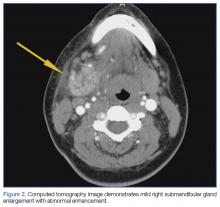

A soft tissue neck computed tomography (CT) scan with contrast was obtained, which revealed mild right submandibular gland enlargement with abnormal enhancement (Figure 2). Stranding was also noted in the right submandibular space along with thickening of the right platysma muscle, and few surrounding lymph nodes were prominent (Figure 3). The findings were consistent with acute submandibular sialadenitis.

As illustrated in our case, CT imaging can assist in confirming the diagnosis of acute submandibular sialadenitis by defining the anatomic involvement and identifying the presence of an abscess. Ultrasound can also be used and has been described as a first-line imaging procedure.7,8

We suspected acute submandibular sialadenitis in our patient based on clinical findings, which were confirmed on CT imaging. Patients with acute submandibular sialadenitis may present with submandibular gland obstruction in the absence of bacterial infection. Noninfectious obstruction typically presents as pain associated with eating and swallowing, whereas infectious cases include constant pain and tenderness in the affected area. In addition, patients with infectious etiology may also have purulent discharge from Wharton’s duct, fever, chills, and an elevated WBC. Several bacteria have been isolated, the most common being S aureus. However, streptococci, P aeruginosa, M catarrhalis and E coli have also been identified. Computed tomography studies are helpful in confirming the diagnosis, defining anatomical involvement, and in identifying abscess formation.